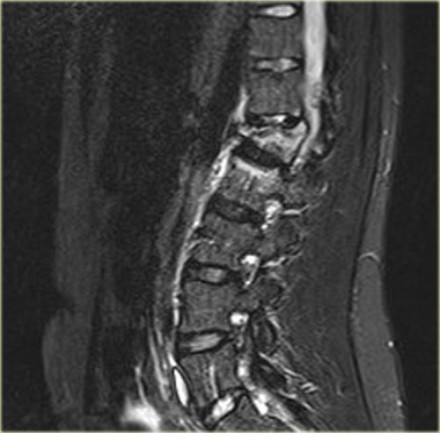

The findings are:

- The morphology is of a vertebral fracture with retropulsion of a fragment, i.e. burst (2 points)

- The PLC is injured with edema of the interspinous ligament and a torn flaval ligament (3 points).

Based on imaging alone, the TLICS score is 5 points and this patient is a surgical candidate.